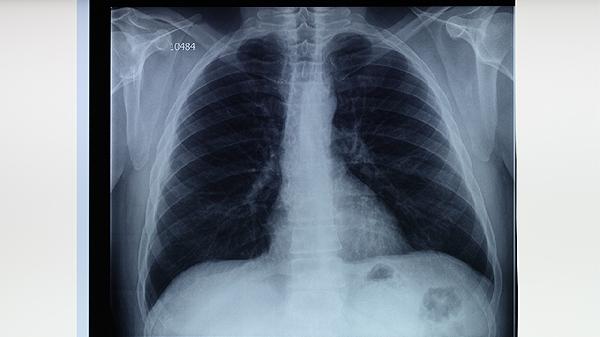

每半年进行胸部X线或结核菌素试验检查,出现持续咳嗽、低热、盗汗等症状时及时排查。糖尿病患者肺结核起病常较隐匿,痰涂片检查联合γ-干扰素释放试验可提高检出率。